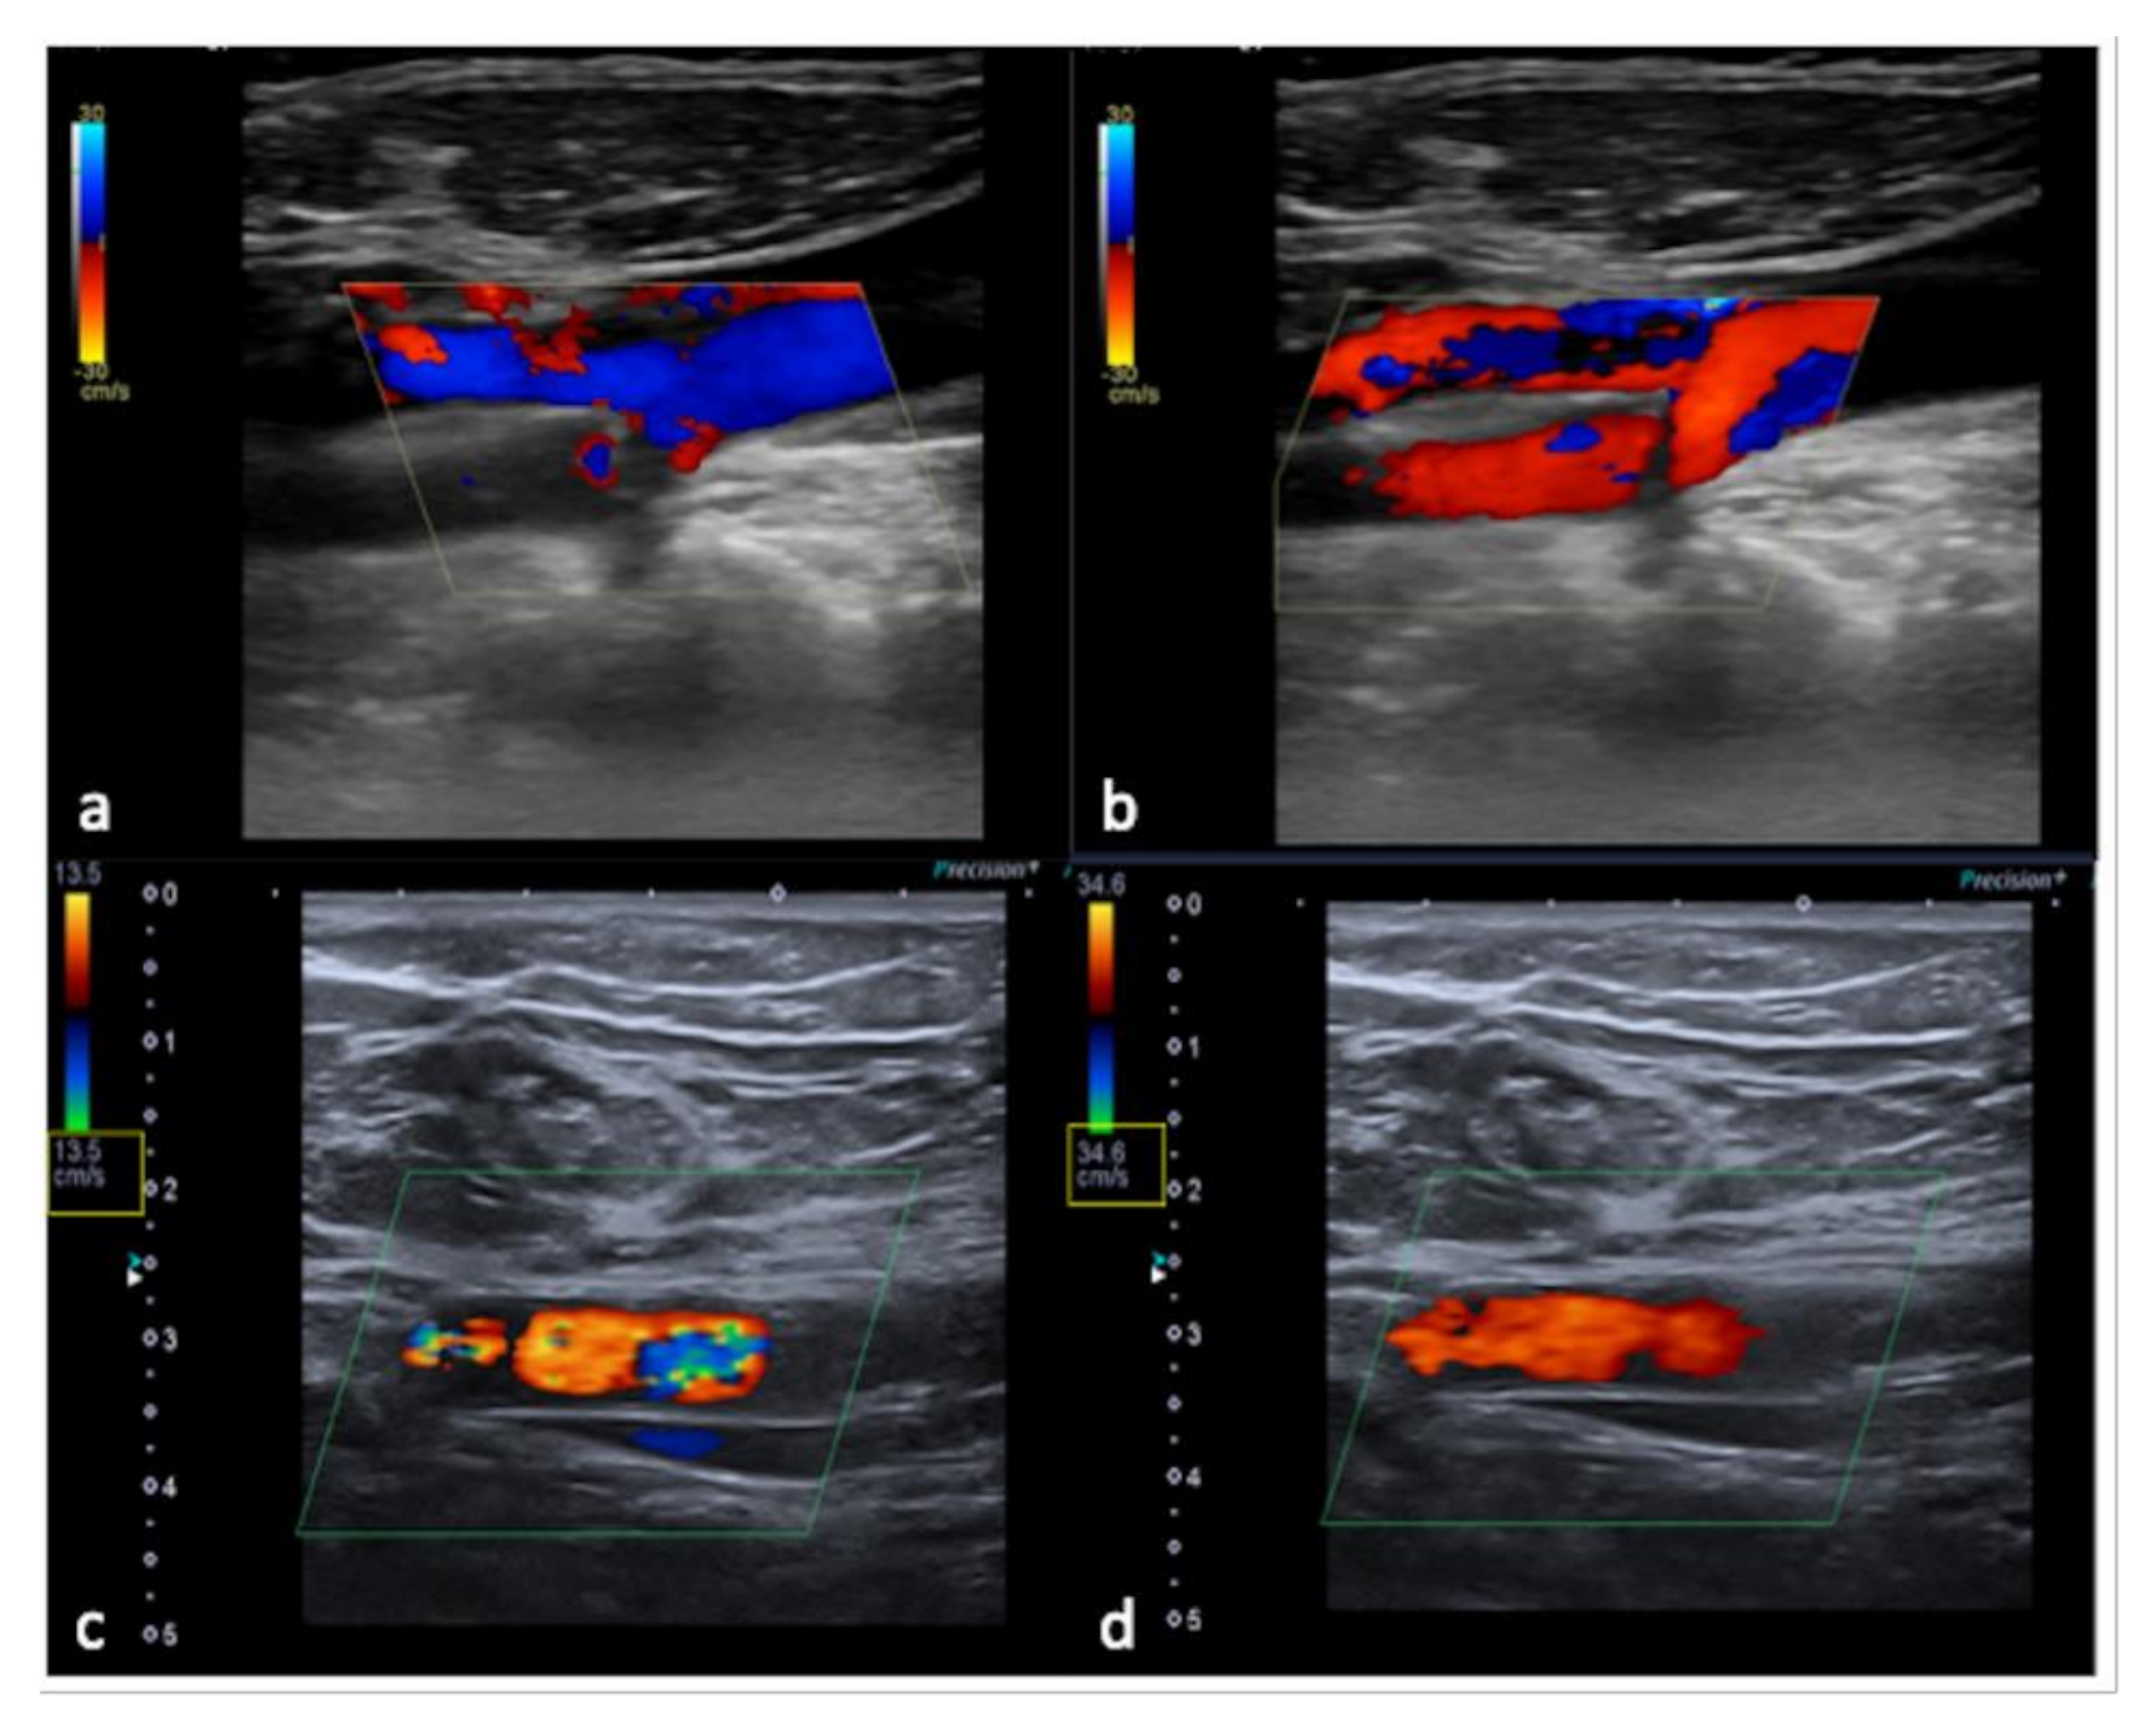

3.3. US-Setting Errors

| Steps | Color and Pulse Doppler Parameter | Remarks |

| 1st | Pulse repetition frequency (PRF) | Optimal PRF proportional to the flow to be studied and in principle must be lowered until it almost reaches the aliasing threshold. |

| 2nd | Size and position of the color box | The color box must be neither too wide, too small, too long nor too deep. |

| 3rd | Angle correction | To calibrate the velocity scale for the angle between the US beam and the blood flow being measured. Ideally, the direction of flow should be at an approximately 45–60° angle relative to the transducer. |

| 4th | Steering | Use probe positioning/beam steering to obtain satisfactory beam/vessel angle |

| 5th | Further settings | Wall filters; inversion of flow; color gain; spectral gain; baseline. |